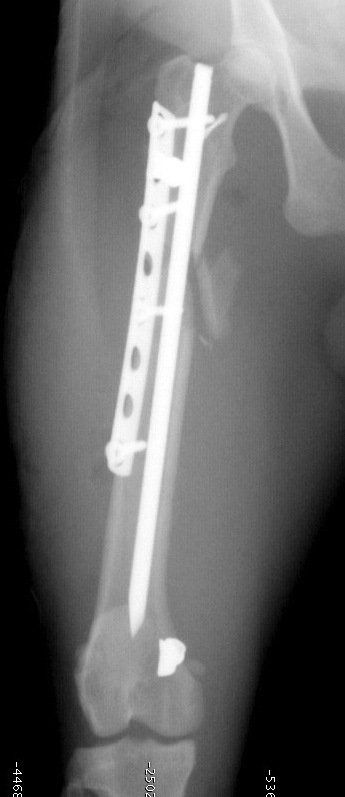

- rekonstruktive Operationen während gebrochene Knochen Gliedmaßen mit Stiften, Platten und Schrauben.